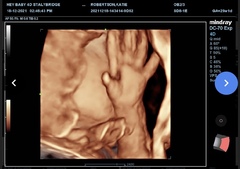

Kt1111 · 19/12/2021 21:51

29 weeks and 2 days now- she got fed up at the 4d scan and put her hand on o cover her face - I love the hbd a foot pic. ♥️ I hope you ladies get some good news soon! Xx